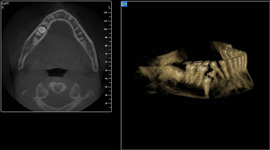

3D DVT - NewTom

Je speciální zubní digitální tříprostorový tomograf (3D), který umožňuje na základě jediného

snímkování vytvořit všechny typy RTG zobrazení, které jsou pro lékaře potřebné. Díky používané technologii tzv. „kuželového paprsku“ a speciálním senzorům je

výrazně zmenšená dávka záření - o více jak 80% proti klasickému CT vyšetření. To je významné zejména u dětí. Pomocí tohoto přístroje je možné zjisti skutečnou situaci v čelistních kostech pacienta tedy množství kosti - můžeme změřit skutečnou šířku i výšku kosti, i kvalitu kosti (hustotu) v místě uvažované implantace. 3D (tříprostorové) zobrazení umožňuje zvýšit prostorovou představu operatéra ještě před vlastní operací a zároveň pacientovi lépe objasnit a ukázat oblast plánovaného zavedení implantátu.

Pacient „neumí číst“ RTG snímky, ale díky 3D zobrazení vidí „svoji skutečnou čelist“

- např. jak je nízká či úzká, vidí průběh nervu nebo velikost čelistní dutiny, což mu umožní i pochopení nutnosti v některých případech provést pomocné zákroky ještě před vlastním zavedením implantátu (viz. kostní štěp, sinus lift, kostní granulát...).

Vyšetření pomocí tohoto přístroje používáme i ve stomatochirurgii (zlomeniny čelistí, zuby moudrosti, cysty, onemocnění čelistního kloubu), ortodoncii (retinované zuby, nadpočetné zuby), parodontologii atd.